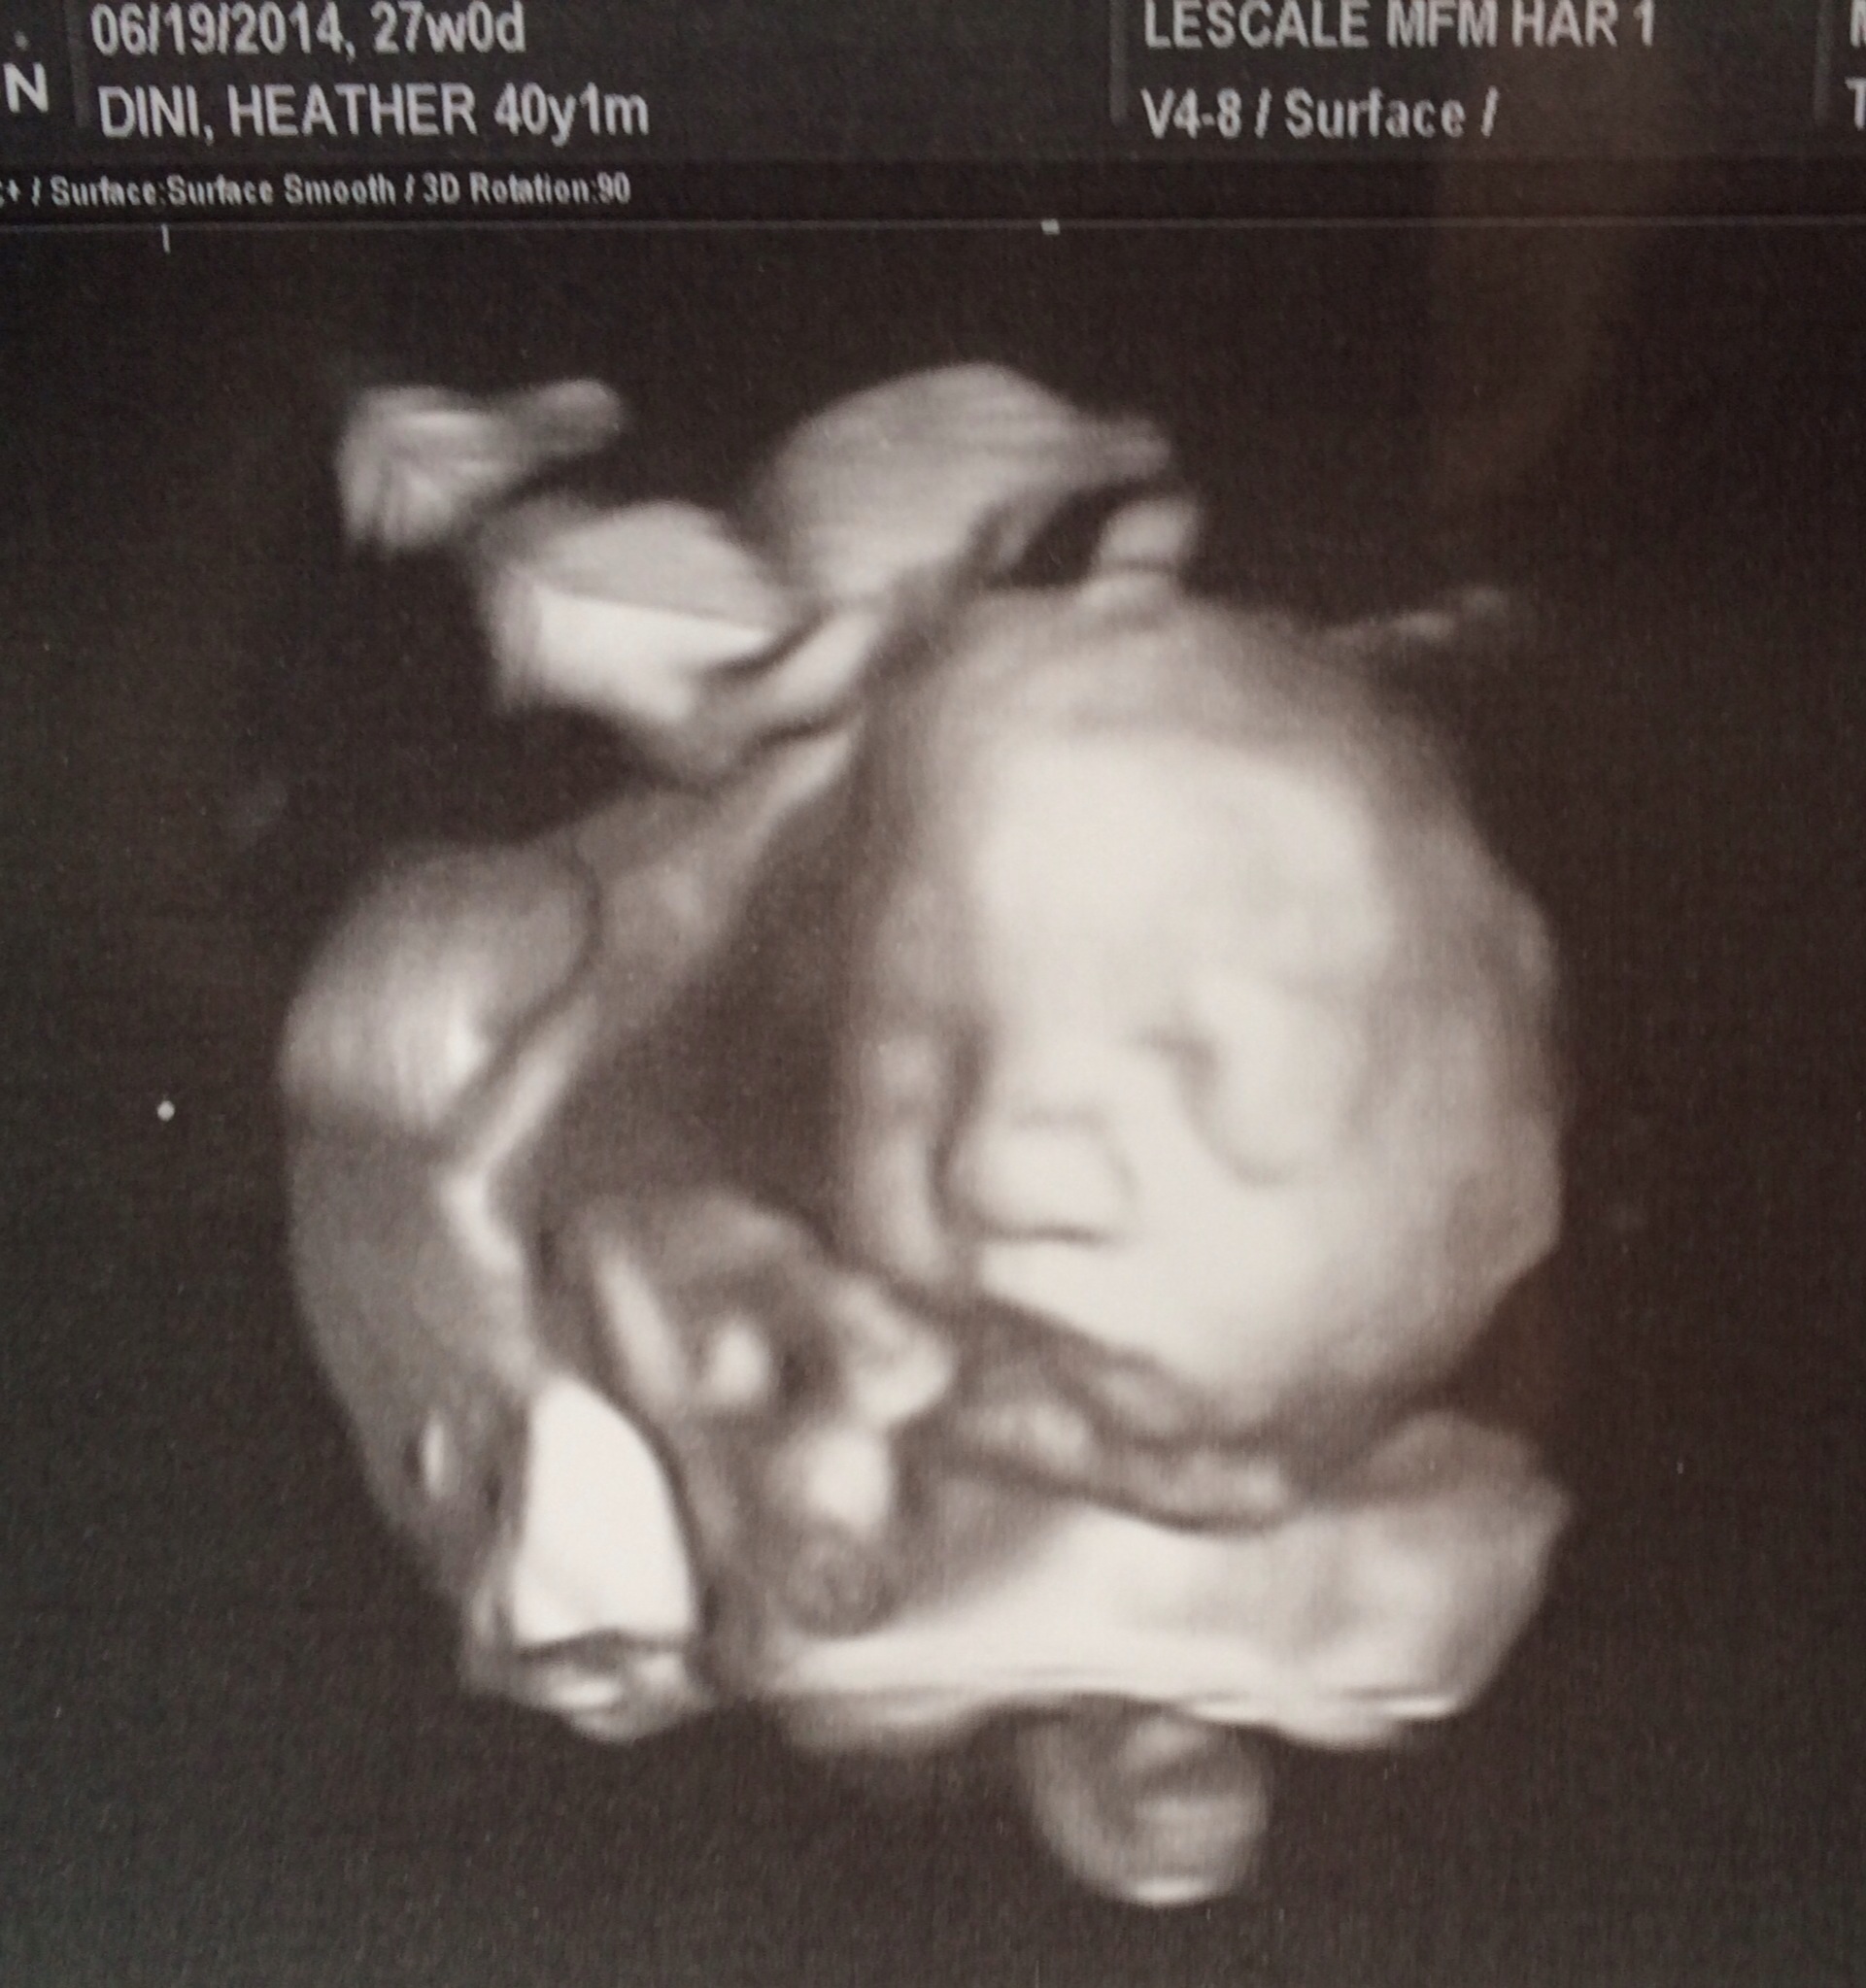

I just had to post. Had my US today. Checking to see if my placenta moved. It did!!

Baby is still breech but doing great!!

Here is the US and 3D US could not wait for the 3D. Super excited. My mom went with me. I'm her only child and I am 40. Lol